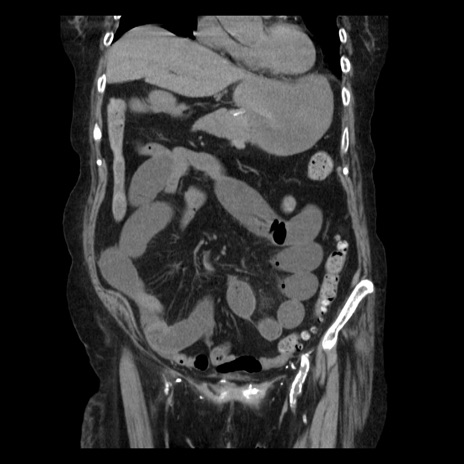

症例14(冠状断像)

【症例】 90歳代女性

【主訴】 腹痛・嘔吐

【現病歴】今朝から左側腹部痛を認めた。 経過観察していたが、嘔吐を認めたため来院。

【既往歴】 子宮癌術後

【身体所見】 意識清明、BP 127/54mmHg、P 98bpm Sp02 95%(RA)、BT 35.8°C、腹部平坦・軟腸ぜん動音聴取良好、右下腹部圧痛(+) 反跳痛なし

【データ】WBC 9800、CRP 0.46